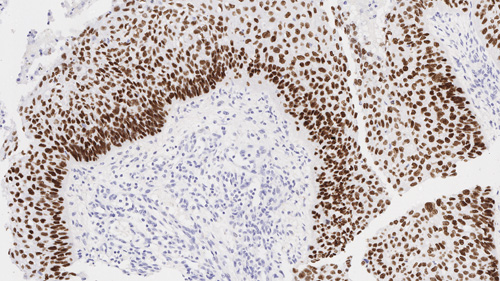

Human colon, ulcerative colitis: immunohistochemical staining for CD16. Note intense membrane staining of infiltrating natural killer cells, granulocytes and activated macrophages. CD16: clone 2H7

CD16 antigen has a molecular weight of 50 to 70 kD and is a low affinity Fc receptor for complexed IgG, Fc/gamma RIII, expressed on natural killer (NK) cells, granulocytes, activated macrophages and a subset of T cells expressing alpha-beta or gamma-delta T cell antigen receptors. The CD16 antigen exists both as a glycosyl-phosphatidylinositol (GPI)-anchored protein in polymorphonuclear cells and as a transmembrane protein in NK cells.